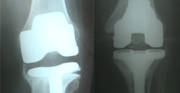

16 Feb 2021- It means to remove the old implant and put a new one.

- When we improve the implant, part of the bone comes out, and ligaments get stretched. So the implant that we put will be of the next level, i.e., more constrained